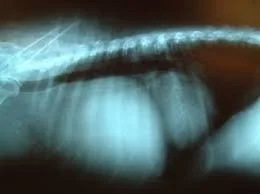

Canine Thymoma: Symptoms, Diagnosis and Treatment

Understand thymoma in dogs—what symptoms look like, how vets identify chest tumors, and the treatment options that may help improve breathing and comfort.